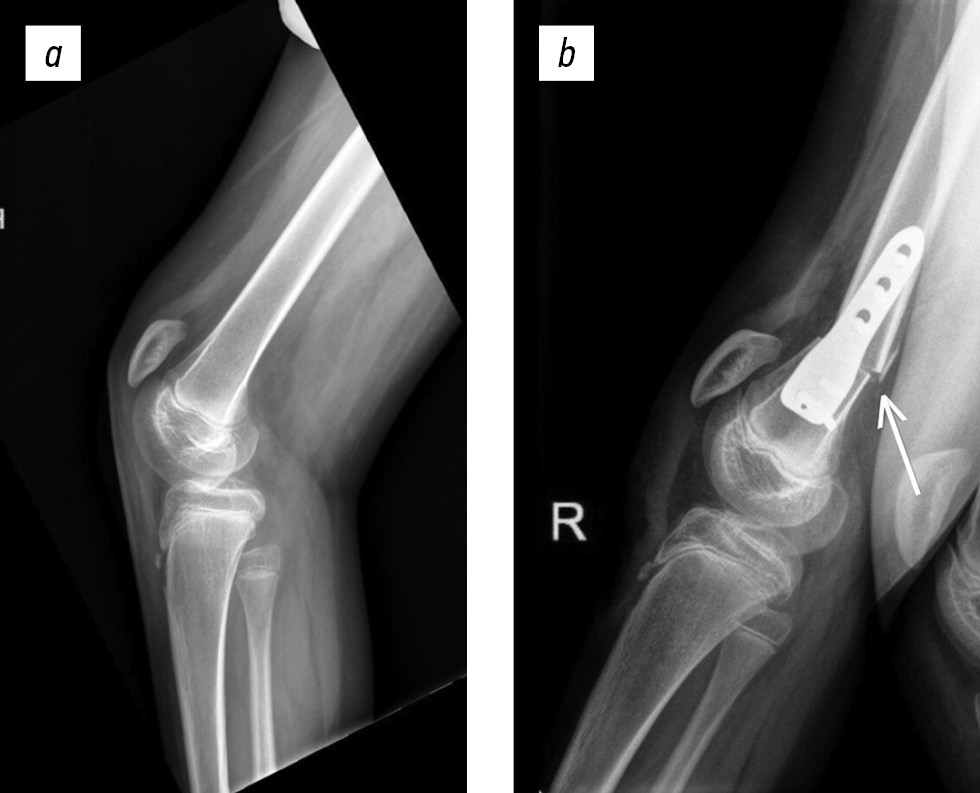

DFSO presents various technical challenges. For KFC up to 30°, wedge-shaped extension osteotomy of the femur is recommended. In particular, Morais Filho et al. [53] modified the wedge osteotomy technique by preserving the posterior cortical bone, which increases the stability of the osteotomy site. In cases of severe contracture (>30°), trapezoidal femoral shortening is preferred, as it is beneficial for minimizing the risk of traction injury to the neurovascular bundle during single-event correction of KFC (Fig. 4). The degree of femoral shortening corresponds to the severity of the contracture [52–55].

Fig. 4. Lateral knee radiographs: a, preoperative radiograph showing a 30° knee flexion contracture; b, postoperative radiograph following distal femoral supracondylar extension-shortening osteotomy. The arrow indicates the angular deformity of the distal femur.

Shortening of the distal femur is an effective surgical technique that helps prevent traction-related complications; however, unlike wedge osteotomy, it does not limit knee flexion, which is crucial for preserving the range of motion. Bleck et al. [51] recommended performing DFSO in cases of recurrent contracture when hamstring lengthening and posterior capsulotomy of the knee joint proved ineffective. Later, a similar approach was described by Morais Filho et al. [53], and Miller [8] emphasized the effectiveness of DFSO for KFC >15° in older patients.